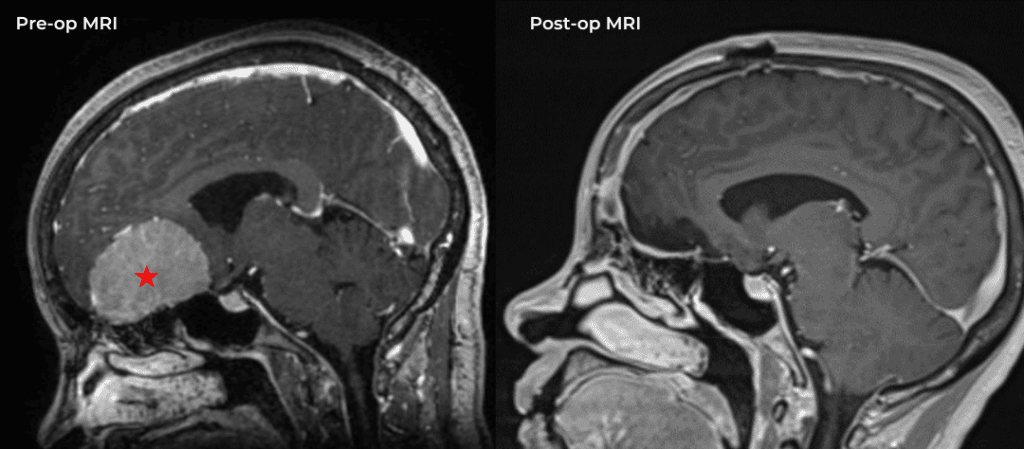

Brain:

Neurosurgeons Collaborate to Treat Giant Symptomatic Meningioma

Author: Ramin Rak M.D., F.A.A.N.S., F.C.N.S., Jonathan L. Brisman M.D., F.A.C.S., Read More!